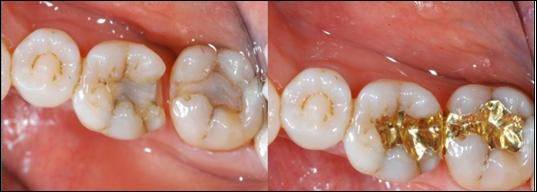

골드 인레이는 정확한 치면과의 접촉과 접착제를 이용한 부착으로 미세 누출이 적기 때문에 장기 예후면에서 가장 유리하다.

금이 장기간 치아 수복물로 애용되는 가장 큰 이유는 귀금속이라 부식이 적고 치아의 법랑질과 강도가 매우 흡사해 닳는 속도가 비슷하기 때문이다. 거기에 구강 밖에서 만들어지기 때문에 치아끼리 맞닿는 부분의 형태를 정확히 재현해 낼 수 있기에 음식물이 끼는 현상 역시 가장 적다.

골드 인레이의 단점은 우선 엄청난 고가에 있다. 다음으로 모든 재료 중 가장 많은 치아 삭제량과 비심미적이라는 단점 역시 가지고 있다.

환자가 경제적인 여유가 된다면 일반적으로 구치부 수복에서 가장 좋은 재료는 골드 인레이이다.

레진 인레이는 골드 인레이와 레진의 단점을 보완한 술식이다. 골드 인레이의 비심미성과 레진의 약한 강도, 인접치와 닿는 부위의 형태 수복의 어려움을 해결했다.

레진 인레이는 골드 인레이와 마찬가지로 치아삭제량이 많다는 것과 고가라는 단점을 가지고 있다. 여기에 구강 내 환경에 가장 잘 맞는 재료인 금이 아닌 레진을 사용했기 때문에 치아와 닳는 속도가 비슷하다는 골드의 장점을 잃어버렸다는 단점 역시 가지고 있다.